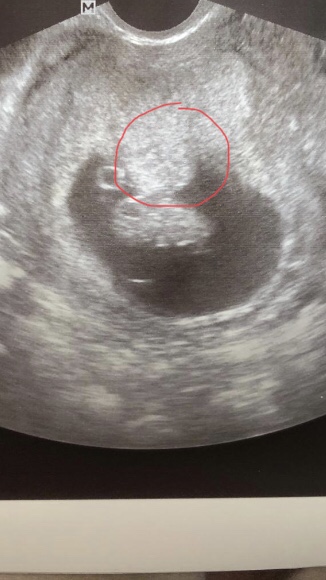

Zdravím vás děvčata. Mám na vás otázečku. Jsem v 9tt po úspěšném IVF/ET. Prcek je v pořádku, roste jak má a srdíčko bije jak o život ale v děloze mám od začátku těhu jaký si výrůstek asi zřejmě v místě kde se Drobek zavrtal. Při transferu byla děloha čistá. Doktoři to zatím moc neřeší, jen to hlídají a čeká se na 1. Screenink. Chtěla jsem se zeptat jestli jste náhodou neměla některá z vás něco podobného nebo jestli jste se s tim třeba nesetkali. Co by to mohlo být. Jestli to samo zmizelo nebo ne. Jsem z toho trochu nervózní, mám strach aby tam ten výrůstek za chvilku nezačal třeba prckovi vadit jak bude růst a nebo aby mu nějak neublížil. Na screenink jdu až za měsíc a mám obavu ze špatných zpráv. Je to naše vymodlené miminko. Prikládám i fotku. Předem děkuji za všechny odpovědi.